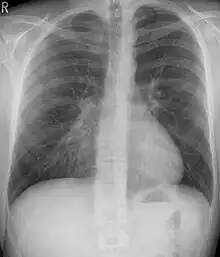

Many scales have been developed to determine the degree of deformity in the chest wall. Most of these are variants on the distance between the sternum and the spine. One such index is the Backer ratio which grades severity of deformity based on the ratio between the diameter of the vertebral body nearest to xiphosternal junction and the distance between the xiphosternal junction and the nearest vertebral body.[17] More recently the Haller index has been used based on CT scan measurements. An index over 3.25 is often defined as severe.[18] The Haller index is the ratio between the horizontal distance of the inside of the ribcage and the shortest distance between the vertebrae and sternum.[19]

Chest x-rays are also useful in the diagnosis. The chest x-ray in pectus excavatum can show an opacity in the right lung area that can be mistaken for an infiltrate (such as that seen with pneumonia).[20] Some studies also suggest that the Haller index can be calculated based on chest x-ray as opposed to CT scanning in individuals who have no limitation in their function.[21]

Treatment

Pectus excavatum requires no corrective procedures in mild cases.[22] Treatment of severe cases can involve either invasive or non-invasive techniques or a combination of both. Before an operation proceeds several tests are usually performed. These include, but are not limited to, a CT scan, pulmonary function tests, and cardiology exams (such as auscultation and ECGs).[23] After a CT scan is taken, the Haller index is measured. The patient's Haller is calculated by obtaining the ratio of the transverse diameter (the horizontal distance of the inside of the ribcage) and the anteroposterior diameter (the shortest distance between the vertebrae and sternum).[24] A Haller Index of greater than 3.25 is generally considered severe, while normal chest has an index of 2.5.[19][25][26] The cardiopulmonary tests are used to determine the lung capacity and to check for heart murmurs.[27]